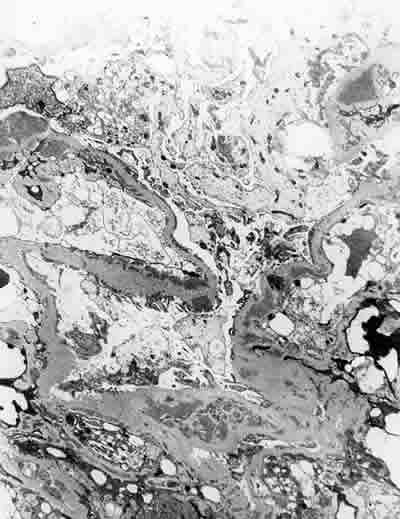

Fig. 10. Microscopia electrónica: extensos depósitos, electrón densos, de localización subendotelial y mesangial. Muy aislados subepiteliales.